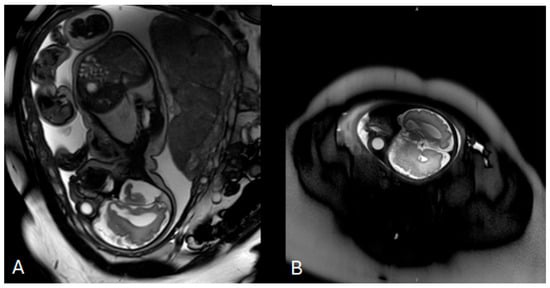

Background: Prenatal detection of fetal structural anomalies often prompts chromosomal analysis; however, chromosomal microarray analysis (CMA) has limited diagnostic yield for monogenic disorders. Whole-exome sequencing (WES) has emerged as a powerful tool for identifying single-gene etiologies, particularly in cases with complex neurodevelopmental phenotypes. Case Presentation: We report a female infant presenting with prenatally detected ventriculomegaly and inconclusive chromosomal testing. Prenatal investigations, including karyotyping and genome-wide chromosomal sequencing, identified several copy number variants classified as variants of uncertain significance but failed to establish a definitive diagnosis. Postnatally, the patient developed progressive neurological abnormalities, including microcephaly, facial dysmorphism, dystonic movements, and severe global developmental delay. Trio-based whole-exome sequencing identified a heterozygous de novo pathogenic missense variant in the DDX3X gene (c.976C>T; p.Arg326Cys), establishing the diagnosis of DDX3X-related neurodevelopmental disorder. Conclusions: This case highlights the diagnostic limitations of standard prenatal chromosomal testing in detecting monogenic neurodevelopmental disorders and underscores the critical role of timely genetic counseling and exome sequencing. Earlier selective implementation of WES during pregnancy could have enabled an earlier diagnosis, improved prognostic counseling, and optimized clinical decision-making. Full article

Show Figures

Figure 1